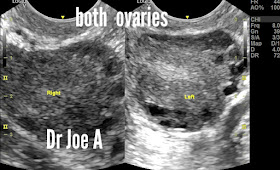

What could be wrong with these ovaries?

Patient of menstrual disorders.

Transabdominal ultrasound showed slightly enlarged ovaries.

TVS ultrasound scan showed these findings:

Ovarian enlargement obvious.

But those follicles are not normal either.

The ovaries are definitely enlarged at 16 and 18 cc. Anything more than 10 cc is definitely in favor of polycystic ovaries.

Peripheral follicles and small follicles are also supportive of PCOD.

Final diagnosis:

PCOD in young woman 👧.